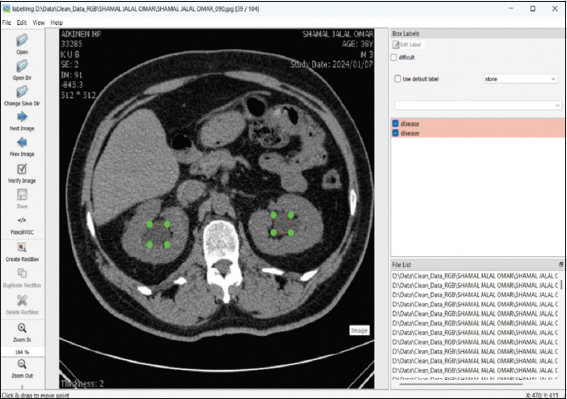

A specialized open-source Python application was utilized for annotating medical CT scans. The labeling process was executed through labelImg.py, a commonly employed annotation tool incorporated within the Anaconda environment. CT scans illustrating nephropathy (Fig. 2) and kidney stones (Fig. 3) were meticulously examined and documented under the direct supervision of a qualified nephrologist to guarantee clinical precision. Every image was carefully annotated, and the labels were stored in three distinct formats: JavaScript Object Notation (JSON), TXT, and Extensible Markup Language (XML). For the purpose of creating precise segmentation masks unique to each annotated image, the chosen formats were meant to improve compatibility with later processes. In medical image analysis, the manual way ensured better annotations, which are necessary for supervised learning models to work.

thumblarge

Fig. 2. Labelling kidney disease.